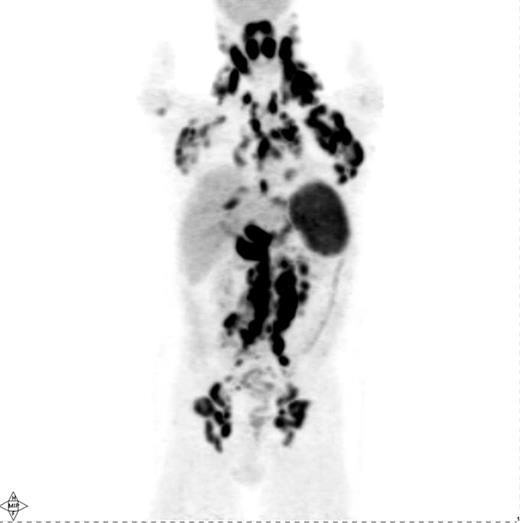

Several investigations have shown that PET is quite sensitive in detecting nodal and extranodal manifestations of HL prior to treatment (Figure 1 ).4,–14 Most of these studies have reported on mixtures of HL and NHL patients, although a few have specifically addressed the utility of PET for staging of HL.6,–13 In aggregate, these studies demonstrate that PET is able to detect an additional number of presumed HL sites compared with conventional staging methods, in particular CT and bone marrow biopsy (BMB). This results in a modification of disease stage (usually upstaging) in about 15–20% of patients with an impact on management in about 5–15%.4,–12 However, one drawback of these studies is that they did not provide histopathological verification of all or, at least most, of the additional PET findings not shown by conventional staging methods. Reports of up- or downstaging patients by PET were mostly based on theoretical considerations that assumed that the additional PET findings truly represented lymphoma.8,9,10,–14 Some studies used the disappearance of abnormal PET up-take following treatment as “proof” of the lymphomatous nature of these additional PET findings, a somewhat problematic approach considering that PET-positive benign entities such as fractures or inflammation may resolve with time irrespective of therapy.8,9,10,–14 Nevertheless, several conclusions can still be drawn, particularly based on the studies in which reported modifications of disease stage or management were based on PET findings verified by biopsy, additional imaging (e.g., MRI) or by posttreatment morphologic regression (by CT) of PET-positive lymph nodes presumed to be normal on pretherapy CT.4,–7,10 First, PET is able to detect focal or multifocal bone/bone marrow involvement in HL patients with negative iliac crest BMB, which could frequently be verified by guided biopsy of the PET-positive sites or by MRI.5,–7,12,15,–17 On the other hand, diffusely increased bone marrow uptake on PET may be due to reactive myeloid hyperplasia characteristic of some HL patients rather than lymphoma.16 In general, even focal/multifocal PET findings in the bone/marrow in the face of negative BMB should be confirmed whenever a change in treatment is contemplated based on PET. Second, PET alone is unreliable in detecting bone marrow involvement, particularly of limited degree (i.e., ≤10–20% of marrow space); an estimate of PET sensitivity for detecting marrow infiltration in HL based on a recently reported meta-analysis was 76% (95% CI 47–92).17,18 PET cannot, therefore, replace BMB in the staging of HL, at least based on currently available data. Third, PET and CT lead to concordant clinical stage in the vast majority of HL patients (60–80%).7,–13 However, several reports suggest that discordant findings occur in both directions: PET demonstrates abnormalities undetectable by CT resulting, on average, in altering stage in 15–20% of patients and CT shows abnormalities undetectable by PET with an impact of a similar magnitude (i.e., 10–20%) on stage assignment.7,–13 Abnormal findings seen only by PET with the potential for modifying disease stage or management include lymphomatous involvement of normal-sized lymph nodes by CT criteria (i.e., ≤ 1 cm in short axis), splenic and hepatic infiltration.4,–14 Although most studies show that PET-negative/CT-positive findings are less common than the reverse, it is clear from a number of investigations that PET alone cannot replace CT for pretreatment staging of HL.7,8,10,12 Rather, the modalities are complementary. Fourth, based on the complementary information from PET and CT, it appears likely that a PET/CT scan, which combines a PET and a CT scan in a single study, performed in the staging setting using i.v. contrast, will provide at least equal information to that provided by PET and a separately obtained i.v. contrast-enhanced CT (CECT) acquired using a dedicated CT scanner. The use of i.v. contrast when performing CT, regardless of whether it is performed as a separate study or as part of PET/CT, enables more accurate CT assessment of the liver and spleen. The adequacy of PET/CT performed under these conditions is supported by mostly retrospective or small trials showing that PET/CT performed even without i.v. contrast provides similar information to that provided by PET and a separately performed CECT.14,19 Thus, a pretreatment PET/CT with i.v. contrast may represent a reasonable choice of a modality providing an integrated functional/ anatomical assessment of HL with the added advantage of facilitating the interpretation of posttherapy PET or PET/ CT scans that are often obtained in patients with HL. However, pretreatment PET (PET/CT) is clearly not mandatory for staging and, while useful for a more reliable interpretation of posttherapy PET, is only fully justified outside of clinical trial setting if its results will alter patient management. Given the increasing reliance on systemic treatment with chemotherapy either alone or combined with radiation therapy (RT) depending on disease stage and certain risk factors (e.g., B-symptoms or bulky disease) PET is increasingly unlikely to result in a change in treatment approach if it demonstrates additional sites of disease or even alters the disease stage.8,10 In this context, it is noteworthy that Meyer et al demonstrated that in patients with nonbulky limited stage HL (clinical stage I and II A) there was no difference in overall survival between patients randomly assigned to receive treatment that includes RT or ABVD alone, making the latter a reasonable and often-utilized treatment option in such patients similar to the treatment utilized in patients with nonbulky advanced stage HL.20 Hence, PET upstaging of limited stage patients treated with ABVD alone would, in most instances, not have any impact on management. Interestingly, however, > 2 or 3 involved nodal regions are considered risk factors in limited stage HL according to the German Hodgkin Lymphoma Study Group (GHSG) and European Organization for Research and Treatment of Cancer (EORTC), respectively, and any extranodal disease is also considered a risk factor by the GHSG. According to treatment schemes recommended by these organizations, these risk factors warrant a more intensive treatment (i.e., a greater number of chemotherapy cycles combined with RT) in patients with nonbulky limited stage HL even without altering the disease stage.12,21 Based on such treatment schemes, PET detection of a greater number of nodal sites or extranodal disease would indeed result in a management change even without changing the disease stage.12

Pretreatment PET scan in a patient with Hodgkin lymphoma showing widespread cervical, axillary, mediastinal, hilar, abdominal and pelvic lymphadenopathy in addition to diffuse involvement of the spleen and focal liver involvement.